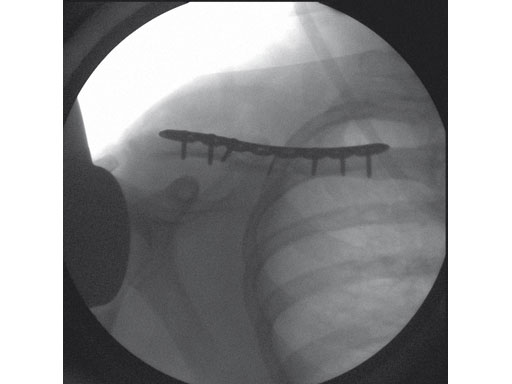

Fig 2ab Postoperative images.